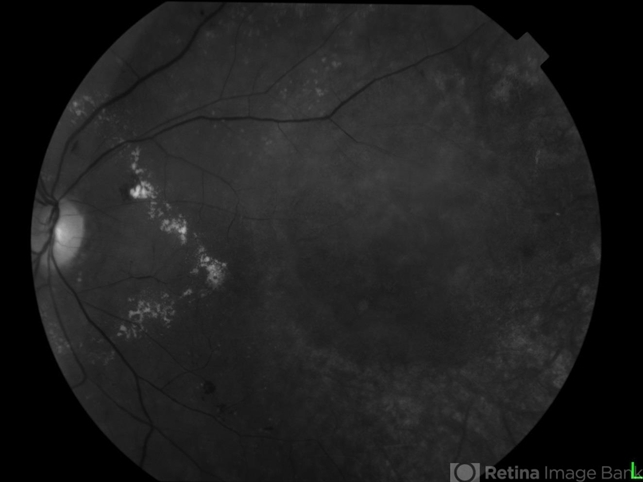

- red-free

Fundus camera

Topcon TRC 50 DX - Description

- Female patient, 53-years-old, diagnosis of choroidal melanoma, already operated in 2009 with brachytherapy.